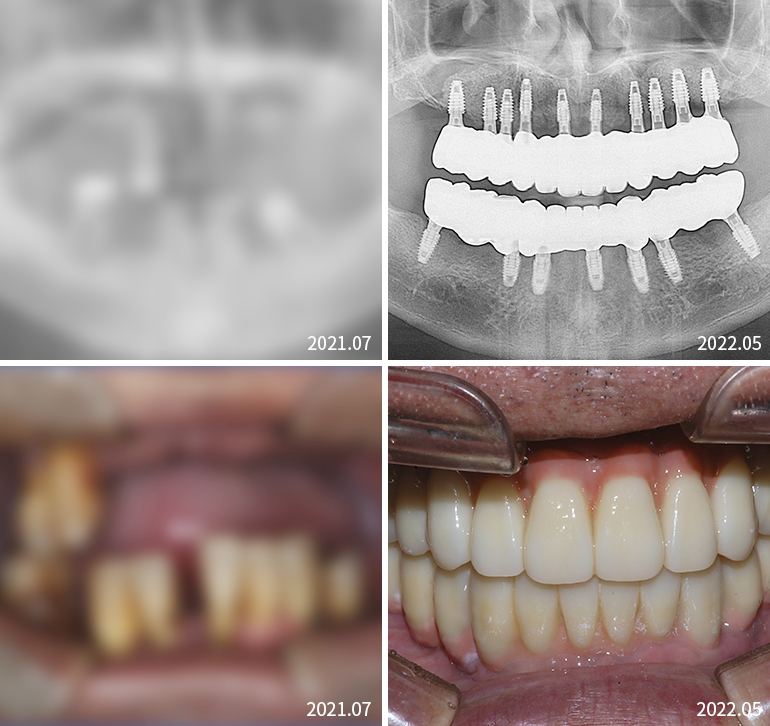

전체임플란트